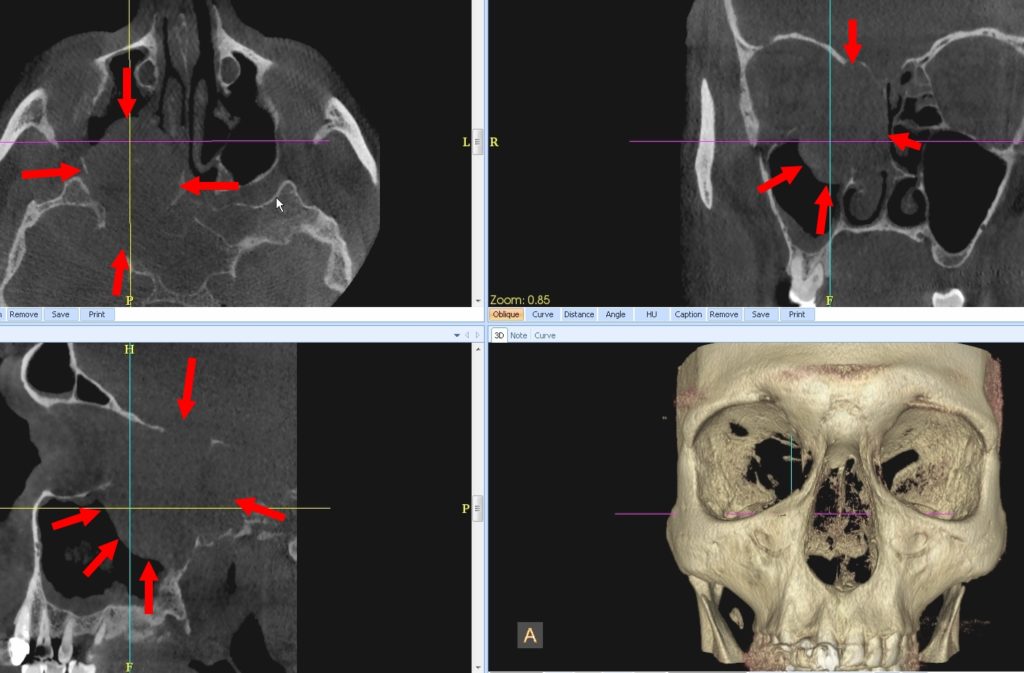

2. La lyse des parois sinusiennes, nasales et orbitaires est très évocatrice de lésion maligne.

3. Dans ce cadre, les deux étiologies les plus fréquentes à envisager sont :

• le carcinome épidermoïde

• et le lymphome.

4. Seule l’histologie, pratiquée sur prélèvement par endoscopie nasale, permet un diagnostic étiologique.

Le bilan d’extension peut être complété par TDM (scanner) et/ou IRM.

Dans ce cas, il s’agissait d’un lymphome de type B, traité par chimiothérapie.

Le patient est en rémission depuis 5 ans.

Une tumeur sinusienne maligne est cliniquement longtemps muette ou s’exprime de façon aspécifique par un dysfonctionnement naso-sinusien, une obstruction nasale ou une épistaxis spontanée. Ces signes plus souvent unilatéraux font pratiquer un CBCT, évocateur s’il montre une masse volontiers volumineuse, hétérogène, plus ou moins irrégulière et surtout lytique sur les parois naso-sinusiennes, et notamment du plancher sinusien et la fosse ptérygomaxillaire. Cet aspect fera discuter les pathologies tumorales malignes et pratiquer une endoscopie et une IRM. Le diagnostic est le plus souvent histologique, révélant les diagnostics suivants :

- Lymphomes non Hodgkiniens (Fig. 2) : il s’agit essentiellement de lymphomes de type B à grandes cellules, diffus dans les sinus maxillaires avec atteintes ganglionnaires précoces et de lymphomes de type T/NK (Natural Killer), plus agressif, dans les fosses nasales. Leur aspect n’est pas spécifique en CBCT ou en IRM et leur diagnostic est surtout histologique.